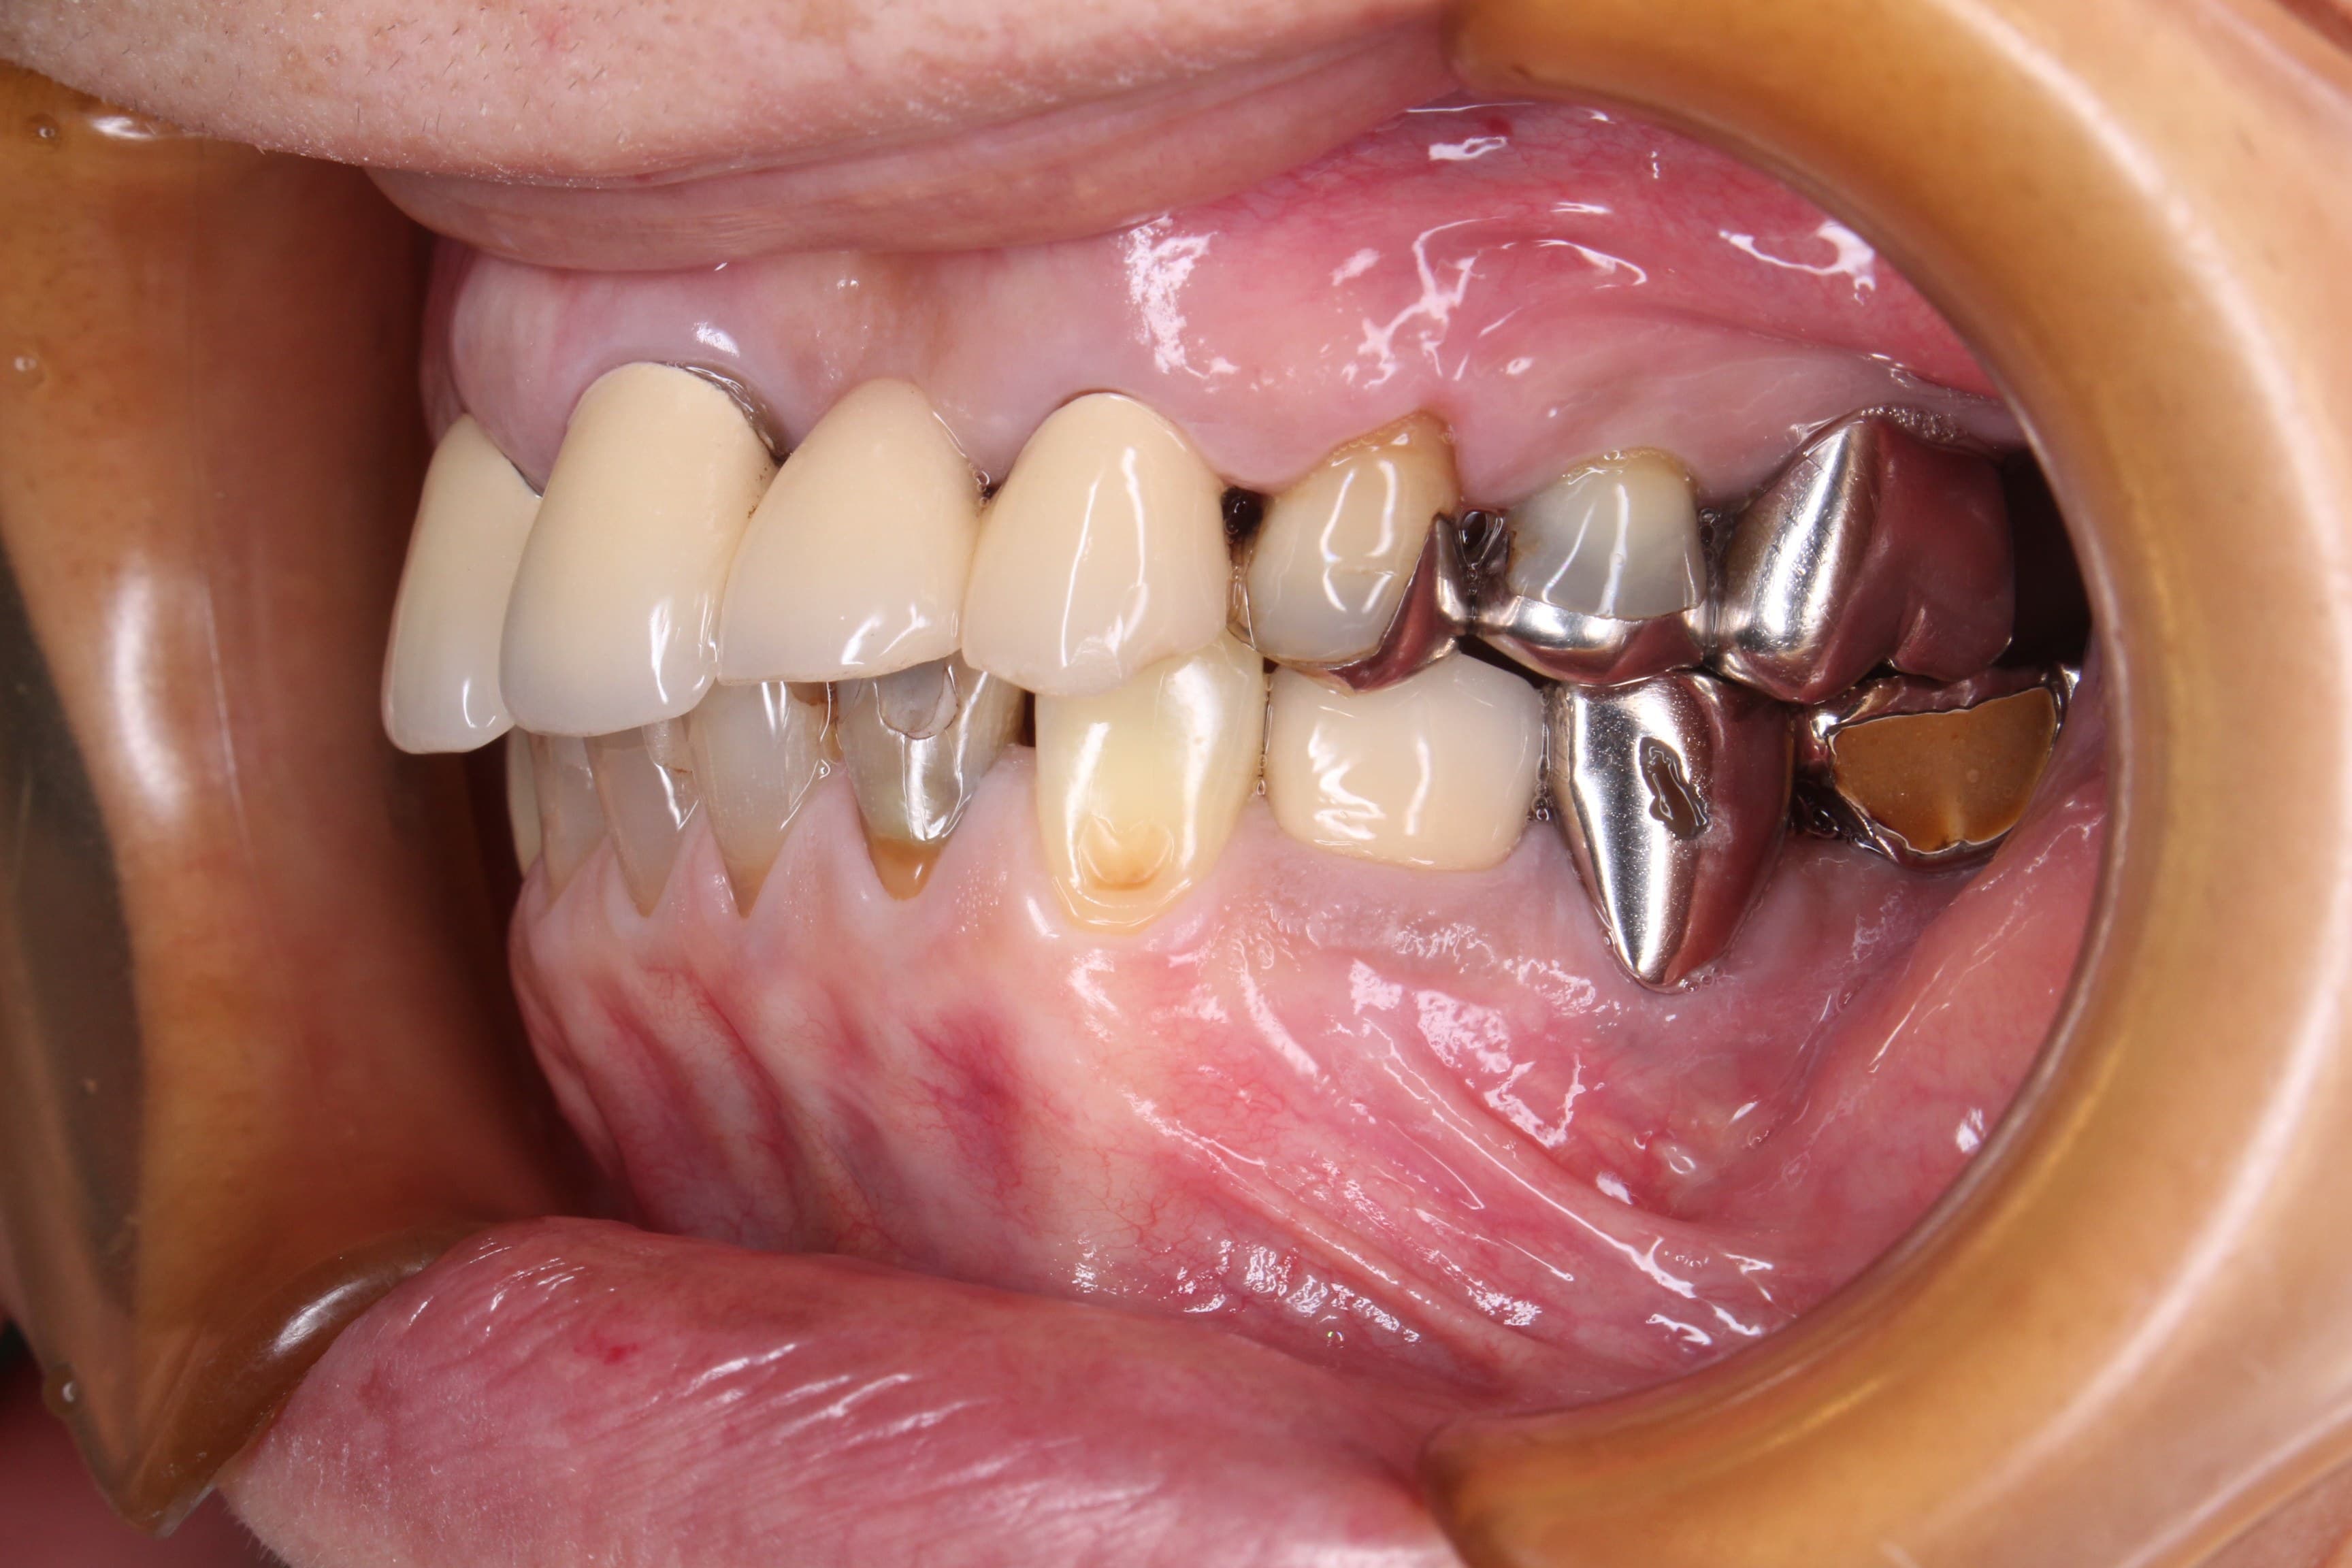

今回ご紹介する歯周専門治療のケースは、60代女性の方です。

数年前に他院で治療した前歯のブリッジが、以前から何度か脱離しており、今回の脱離をきっかけにしっかり治そうと決意して、いらっしゃいました。

治療前

土台に使用していた歯の状態と、噛み合わにも問題があったのですが、非常に出血が多く、先ずは歯周病を改善する必要がありました。